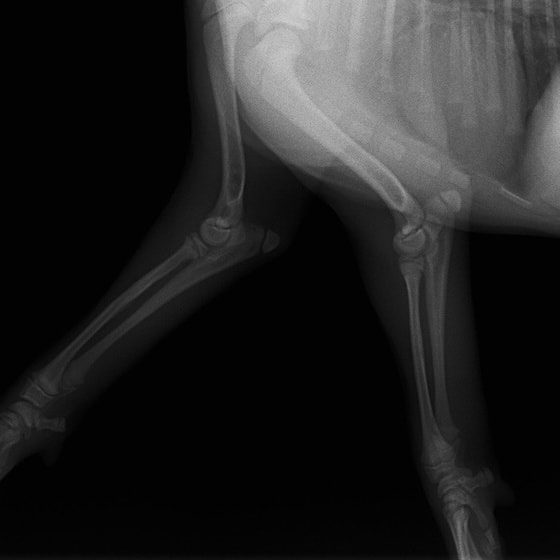

術前レントゲン

術後レントゲン